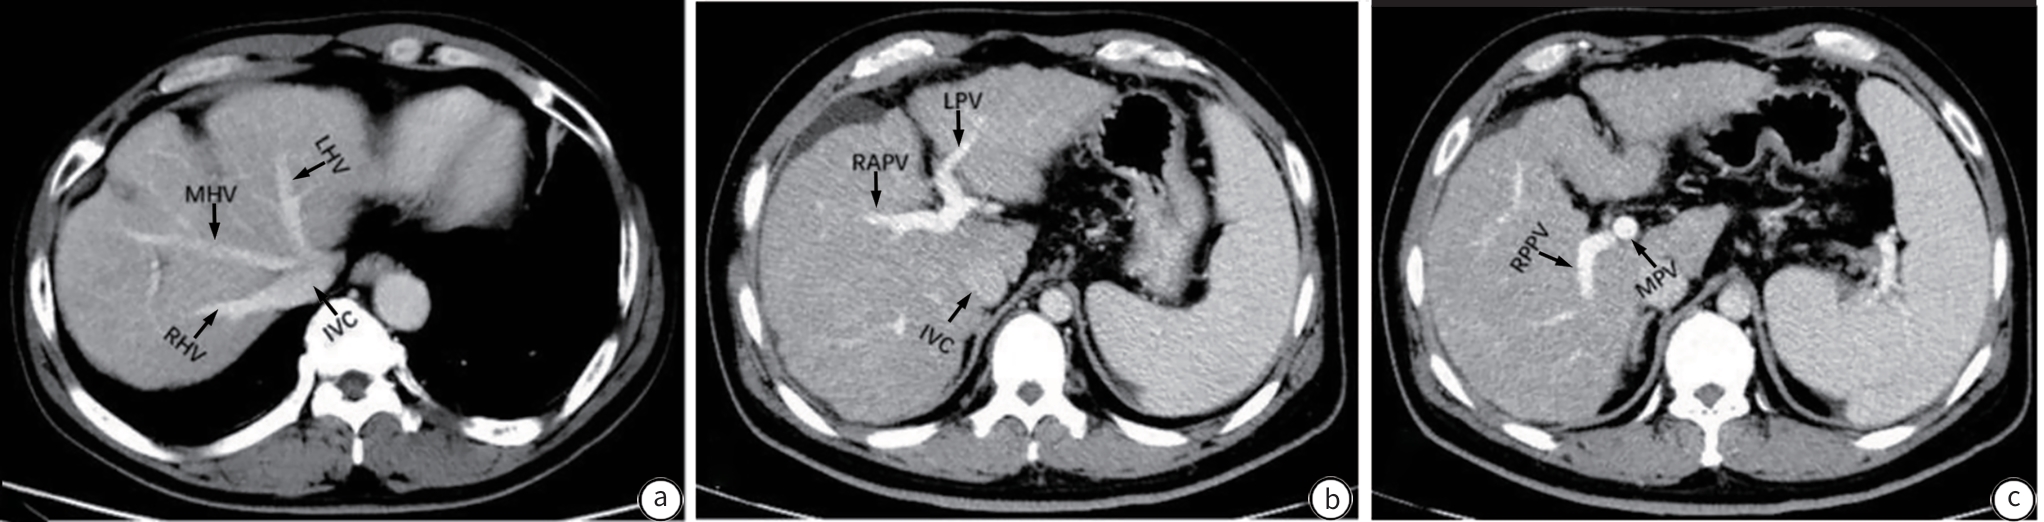

Expert consensus on clinical practice for the diagnosis and treatment of hepatic vascular diseases (2026 edition)

Committee on Liver Diseases (Integrated Traditional Chinese and Western Medicine), China Research Hospital Association, Committee on Interventional Medicine, China Research Hospital Association, Branch for Multidisciplinary Diagnosis and Treatment of Portal Hypertension, Beijing Medical Doctor Association

2026, 42(1): 47-65. DOI: 10.12449/JCH260107

Abstract(886) HTML (478) PDF (1269KB)(477)

Abstract:

Hepatic vascular diseases (such as portal vein thrombosis, porto-sinusoidal vascular disease, hereditary hemorrhagic telangiectasia, arterioportal fistula, and sinusoidal obstruction syndrome, Budd-Chiari syndrome) are characterized by diverse clinical manifestations, difficulties in diagnosis, and various treatment regimens, which brings huge challenges to clinical diagnosis and treatment, and at present, there are still no guidelines or consensus statements on the diagnosis and treatment of hepatic vascular diseases in China. To standardize and improve the diagnosis and treatment of hepatic vascular diseases in China, Committee on Liver Diseases (Integrated Traditional Chinese and Western Medicine) of China Research Hospital Association, Committee on Interventional Medicine of China Research Hospital Association, and Branch for Multidisciplinary Diagnosis and Treatment of Portal Hypertension of Beijing Medical Doctor Association organized the experts in related fields to develop expert consensus on clinical practice for the diagnosis and treatment of hepatic vascular diseases (2025 edition) based on the latest evidence-based medical research and the clinical practice in China, with a focus on the diagnosis and treatment of hepatic vascular diseases.